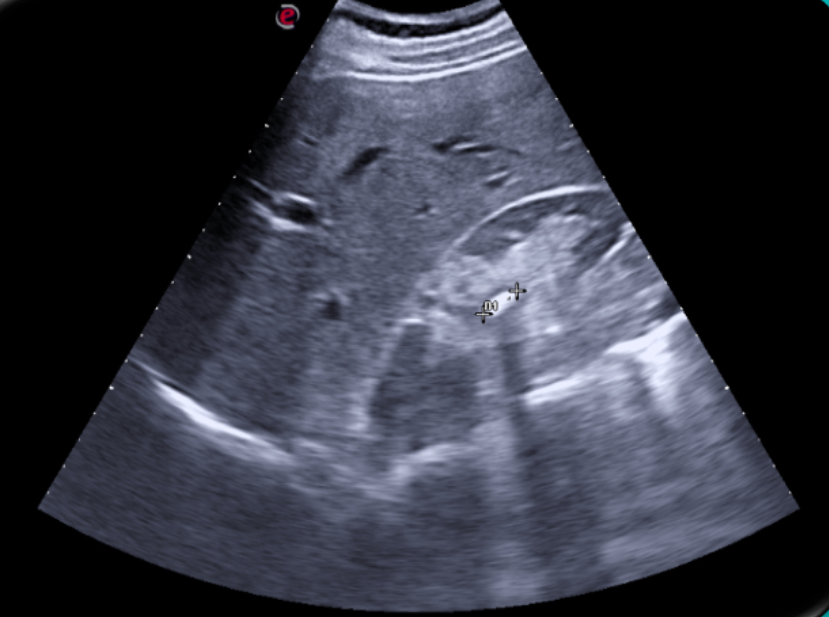

Expondremos la utilidad de la EC como herramienta en el manejo de los pacientes con diferentes tipos de dolor que atiende el Médico de Familia en las consultas diarias, urgentes, e incluso en los domicilios, en diversos escenarios clínicos a los que podemos enfrentarnos en nuestra práctica clínica habitual, desde un dolor visceral (abdominal, torácico, urológico o ginecológico), un dolor músculo-esquelético (traumático o no, con sospecha de fractura u osteoartrósico incapacitante), un dolor vascular (sospecha de trombosis venosa profunda, trombosis arterial aguda, aneurismático); ayudando a obtener una información crucial con un método no invasivo que nos ayudará a reducir la incertidumbre y orientar mejor el diagnóstico de nuestros pacientes e incluso nos podrá ser muy útil como herramienta con fines terapéuticos como en el caso de las infiltraciones ecoguiadas.

En nuestra experiencia como Centro de Salud que utiliza de forma rutinaria la Ecografía clínica, hemos visto un importante avance en nuestra capacidad resolutiva en muchos casos, mejorando el diagnóstico diferencial de los diferentes tipos de dolor, su abordaje terapéutico precoz, e incluso ayudando a los pacientes a una mejor comprensión de su patología.